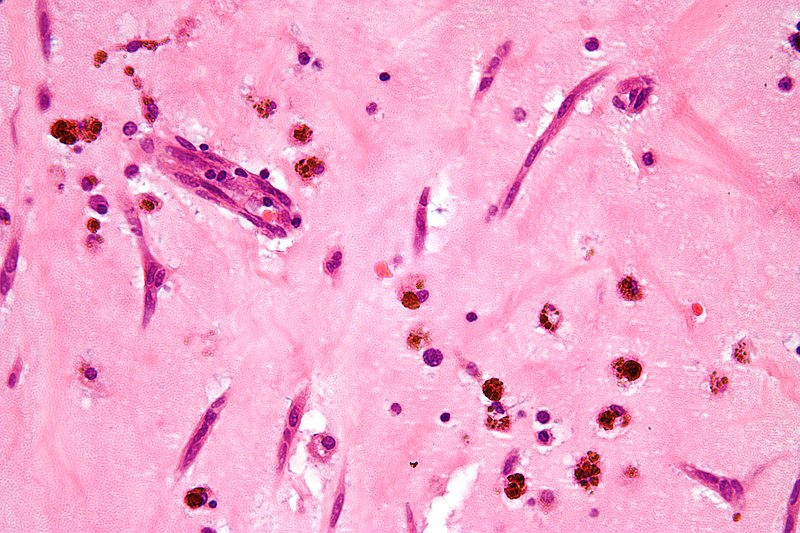

Myxomas typically have a histologic appearance showing an abundance of ground substance and a gelatinous appearance.